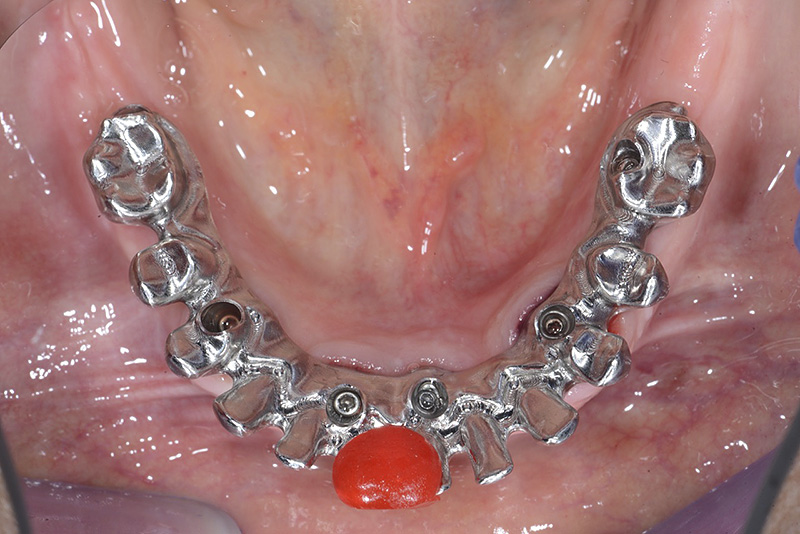

Vengono utilizzati 2 tipi di provvisori: il primo, cementato ai denti vicini, viene utilizzato dal momento dell’estrazione del dente fino ad impianto osteointegrato (circa 6 mesi); il secondo, avvitato direttamente all’impianto, ha una funzione di prova estetica ma soprattutto di guida per la maturazione dei tessuti gengivali peri-implantari portandoli verso la maturazione completa prima di posizionare la corona finale in disilicato di litio.